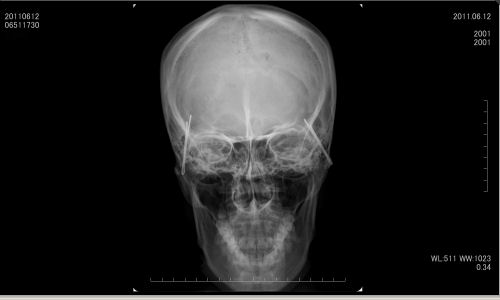

アイドルユニット「ぴゅあふる」の綾川小麦(あやかわ こむぎ)さんが、6月12日に行ったテレビ東京の音楽番組「月刊MelodiX!」の収録中、スタジオの溝に落下する事故で座骨や鼻骨を骨折し重傷を負っていたが、9月2日にライブハウス・渋谷DESEOのライブで元気に復帰した。

ライブ前に綾川小麦さんにお話しを伺うと「鼻骨の骨折は金具で折れた骨を持ち上げ治療を行いました。最初は5倍くらい腫れてびっくりしました。座骨の骨折は治療方法は無く、とにかく安静にすることを病院の先生に指示されました。」と事故後について振り返っていた。